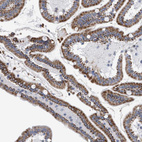

Immunohistochemistry analysis in human kidney and skin tissues using HPA022130 antibody. Corresponding ECI2 RNA-seq data are presented for the same tissues.